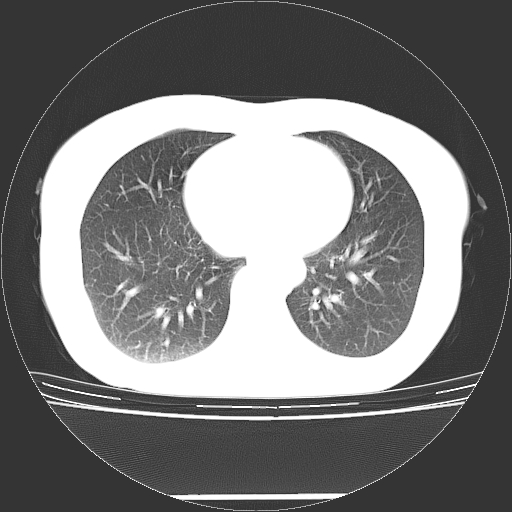

标题: CT27224:女,43岁,体检发现左肺下叶结节影。 [打印本页]

女,43岁,体检发现左肺下叶结节影。

左下肺外带胸膜下见孤立实性均匀密度结节影,边缘光整,增强呈渐进性强化,病灶吴分叶征及毛刺征象;支持硬化性血管瘤。